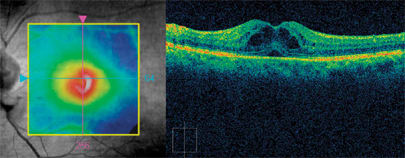

Based on the test results from Cirrus HD-OCT and the patient's initial partial response to anti-VEGF therapy, I chose to continue my current treatment plan: topical NSAIDs and corticosteroids and intravitreal bevacizumab. The patient received a second injection of off-label bevacizumab, and 6 weeks later his vision improved to 20/40 OS with almost complete resolution of central metamorphopsia (Figure 2). I'll continue to monitor the patient every 2 months, or see him as needed if he reports any significant visual change in the interim.

Figure 2. Images from Cirrus HD-OCT show complete resolution of central cystoid macular edema 6 weeks post injection of off-label bevacizumab (Avastin, Genentech).